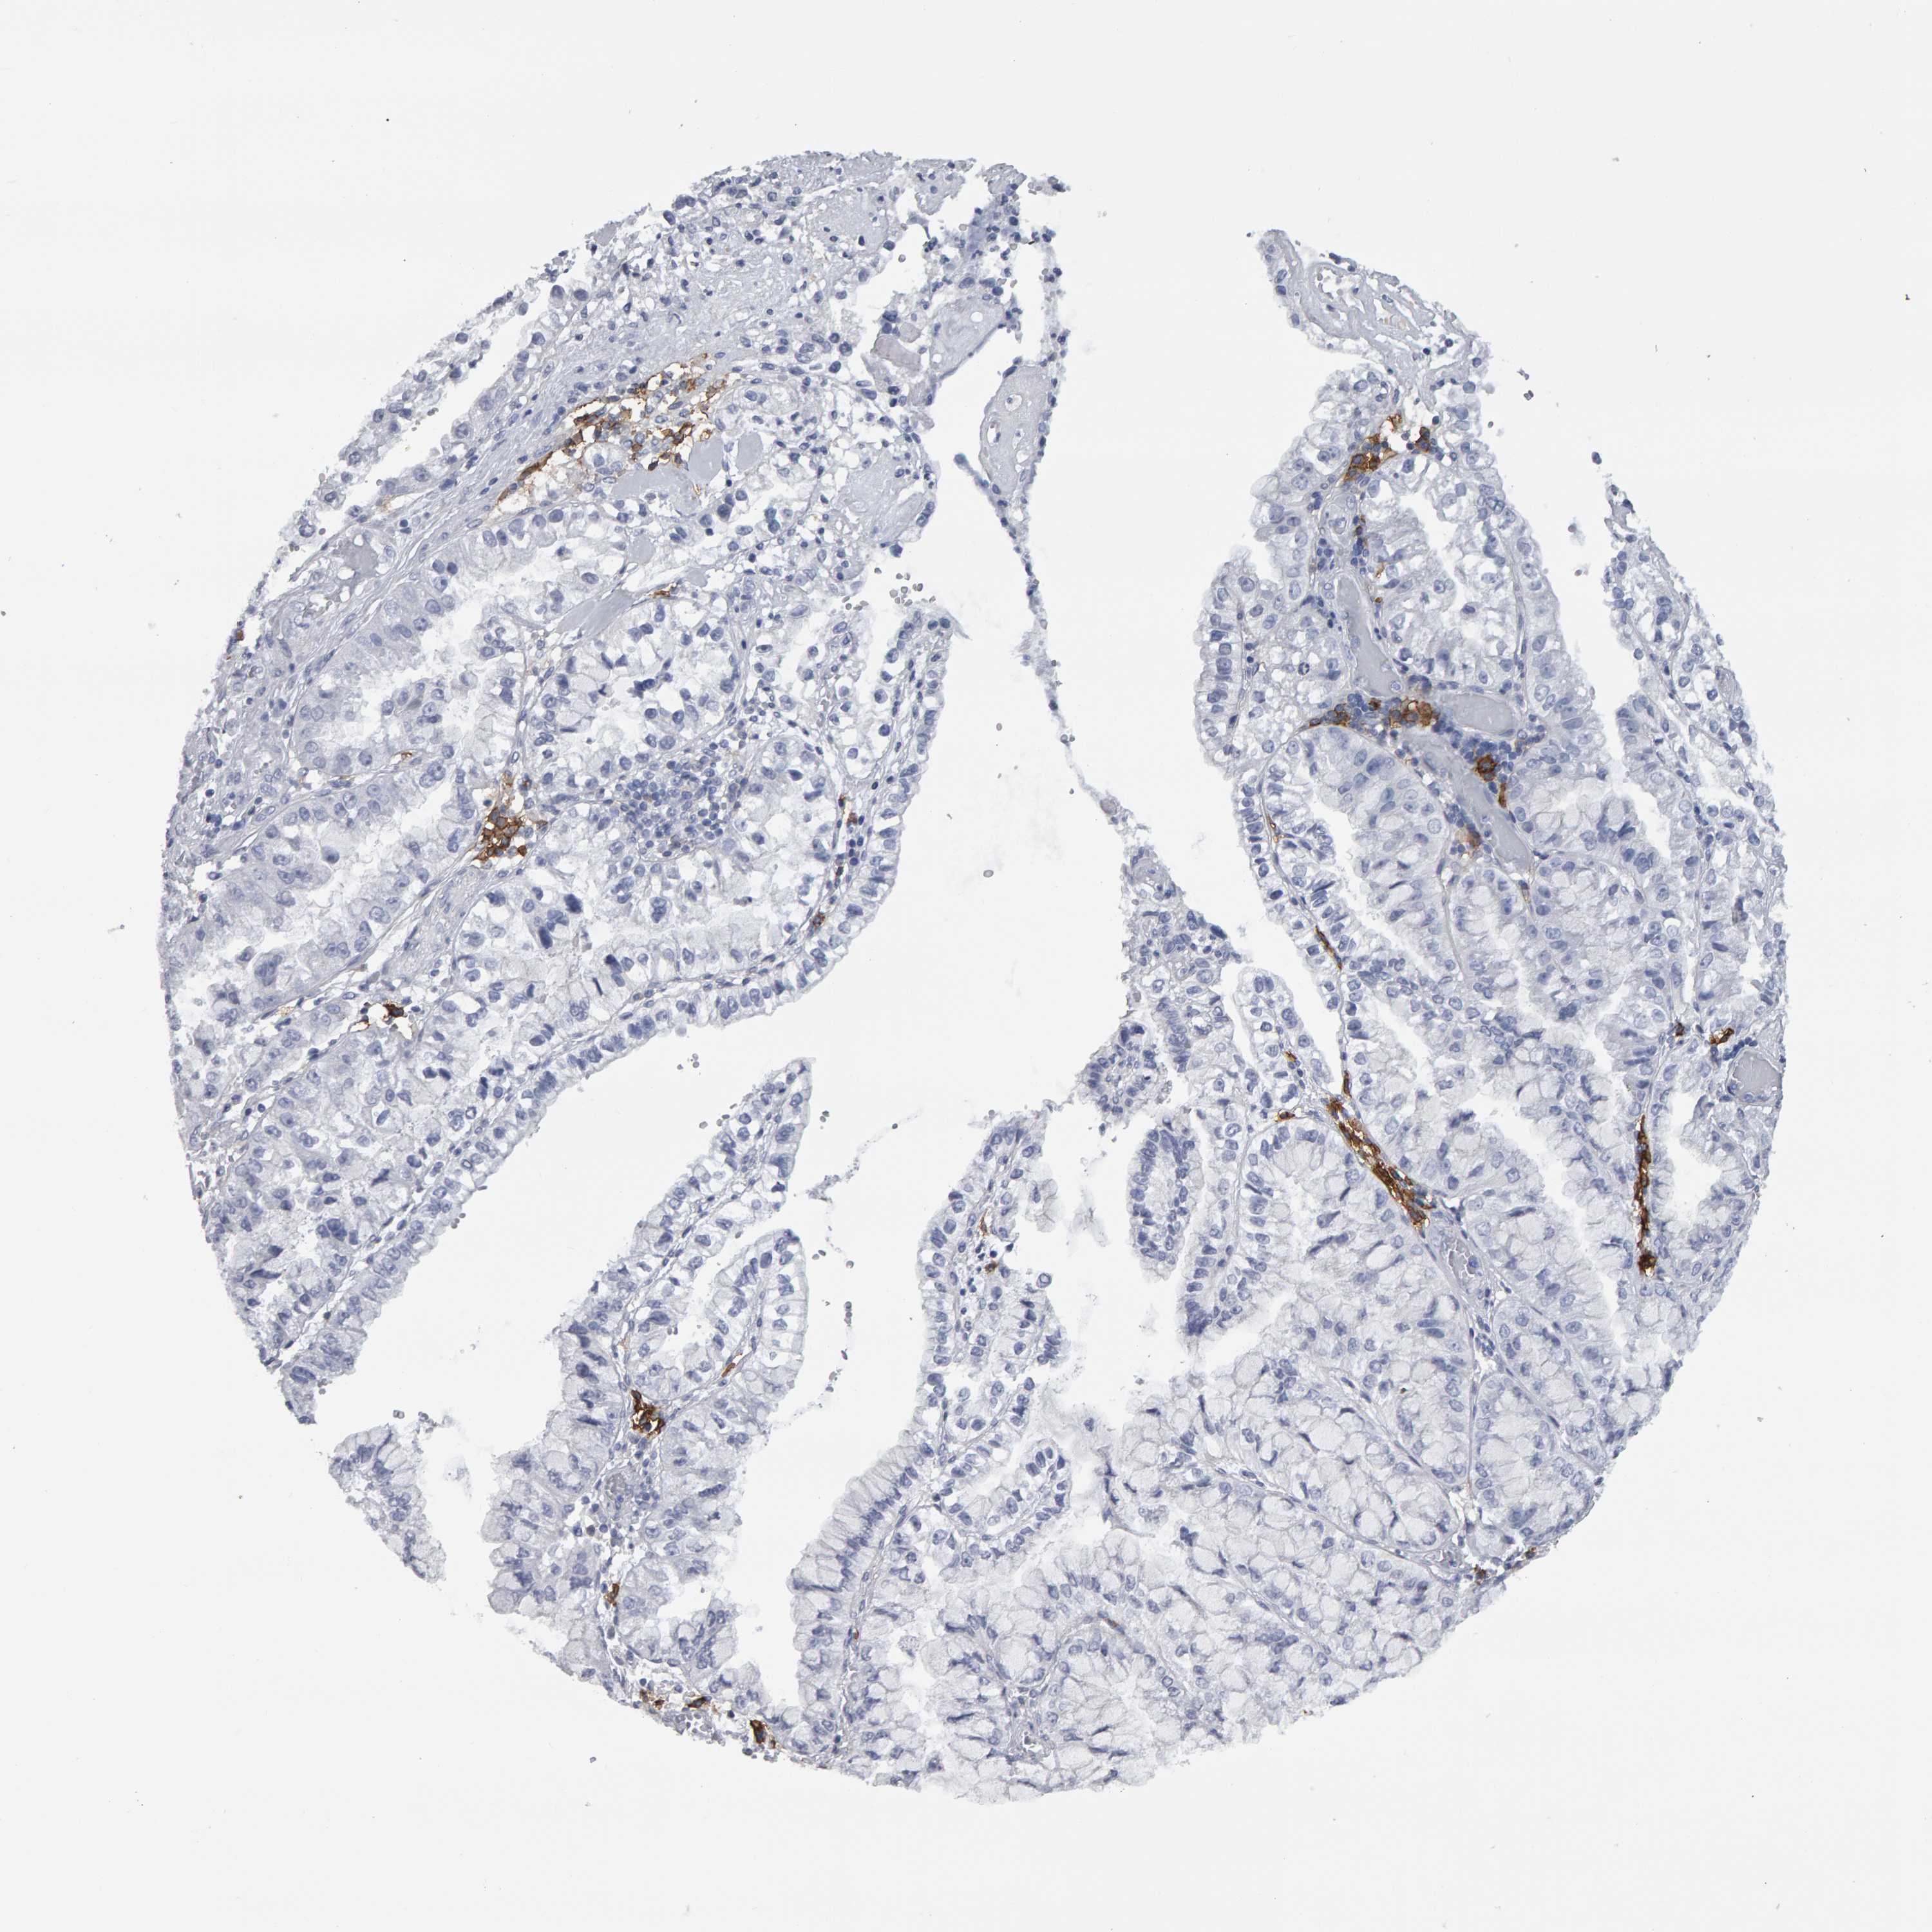

LIVER CANCER - Protein expressioni

A mouse-over function shows sample information and annotation data. Click on an image to view it in a full screen mode. Samples can be filtered based on level of antibody staining by selecting one or several of the following categories: high, medium, low and not detected. The assay and annotation is described here.

Note that samples used for immunohistochemistry by the Human Protein Atlas do not correspond to samples in the TCGA dataset.

Antibody stainingi

Antibody staining in the annotated cell types in the current human tissue is reported as not detected, low, medium, or high, based on conventional immunohistochemistry profiling in selected tissues. This score is based on the combination of the staining intensity and fraction of stained cells.

Each image is clickable and will lead to virtual microscopy that enables deeper exploration of all samples and also displays staining intensity scores, fraction scores and subcellular localization as well as patient and tissue information for each sample.

Antibody HPA022132

Antibody HPA052381

Antibody CAB002493

Antibody CAB025255

Cholangiocarcinoma

Carcinoma, Hepatocellular, NOS